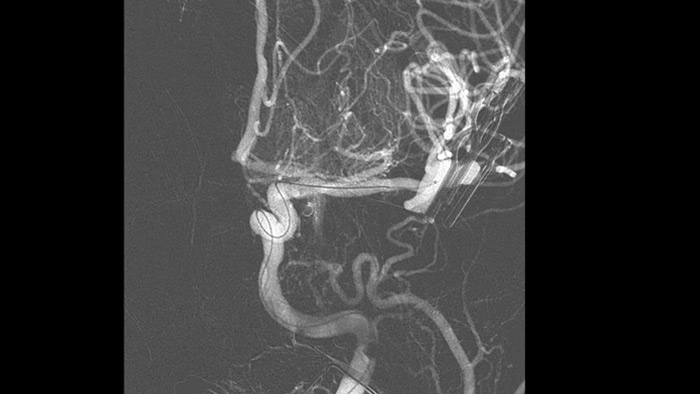

MR-CT Roadmapを使用すると、術前に撮影したSmartCT AngioまたはCT、MRで撮影された画像をライブ透視にオーバーレイして、病変部の境界とそれに対応する血管新生を視覚化し、リスク評価を役立てることができます。事前に収集したデータを再利用することで、患者被ばく線量と造影剤使用量の管理に役立ちます。

Roadmap Proは、放射線被ばくとのバランスを保ちながら、重なり合う血管の視認性を向上させる高度なロードマップです。コイル留置中の進行状況に合わせてカスタマイズできます。